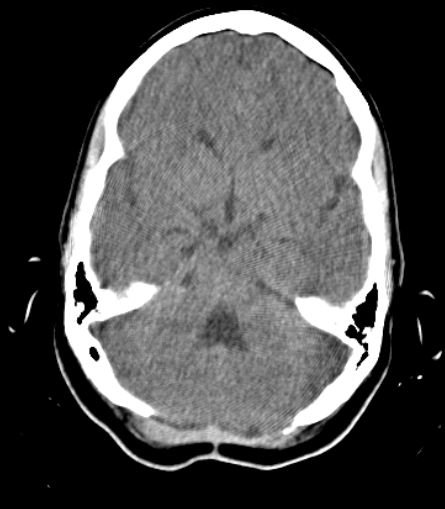

Se realizaron estudios hematológicos que no mostraron alteraciones: hemoglobina 115 g/l, leucograma 6.5x109/l, velocidad de eritrosedimentación 10 mm/h, conteo de plaquetas 250x109/l. Se realizó estudio de TAC simple y contrastada de cráneo (Figura 1) que mostró la presencia de una lesión ocupativa de espacio (LOE) infratentorial, en línea media, retrocerebelosa, de 42x37 mm de diámetro, hipodensa con atenuación LCR (10 UH), bordes regulares y bien delimitados, con efecto de masa pues ejercía compresión y desplazaba el IV ventrículo anteriormente generando hidrocefalia obstructiva. No había presencia de edema perilesional, ni se observaba lesión nodular. No se observó captación tras la administración de contraste. No se realizó estudio de RMN de cráneo por no disponibilidad.

Fig.1. TAC simple de cráneo. LOE quística de fosa posterior. Hidrocefalia obstructiva.

Se realizó el diagnóstico diferencial con otras lesiones quísticas de fosa posterior. Se descartó la posibilidad de una lesión neoplásica: no son frecuentes en la edad de la paciente, la lesión no presentaba nódulo mural, edema asociado ni captaba contraste. Se descartó la megacisterna magna pues no cursa con hidrocefalia y el Síndrome de Dandy-Walker pues no existía dilatación quística del IV ventrículo ni agenesia del vermis cerebeloso. Se planteó como diagnóstico presuntivo el quiste aracnoideoinfratentorialretrocerebeloso de línea media.